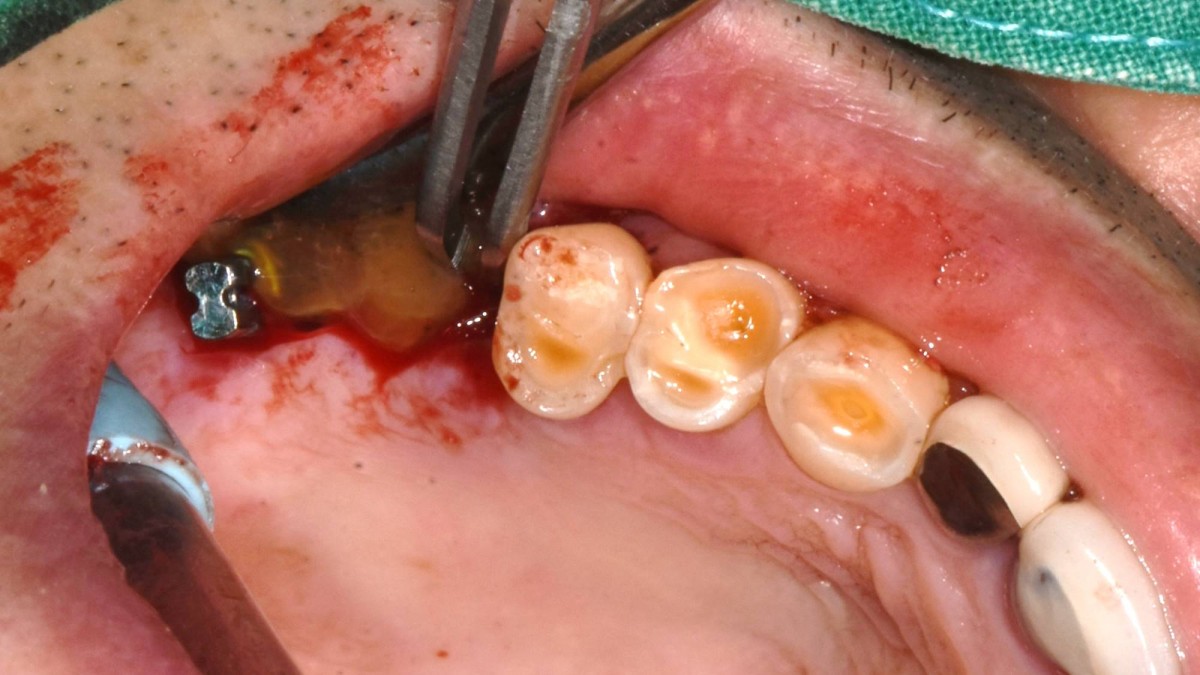

Socket Lift and Implant Placement in the right maxilla.

<GCacg> A 56-year-old male patient complained of pain in the right upper and lower jaws. And he wanted the upper first molar to be pulled out first.